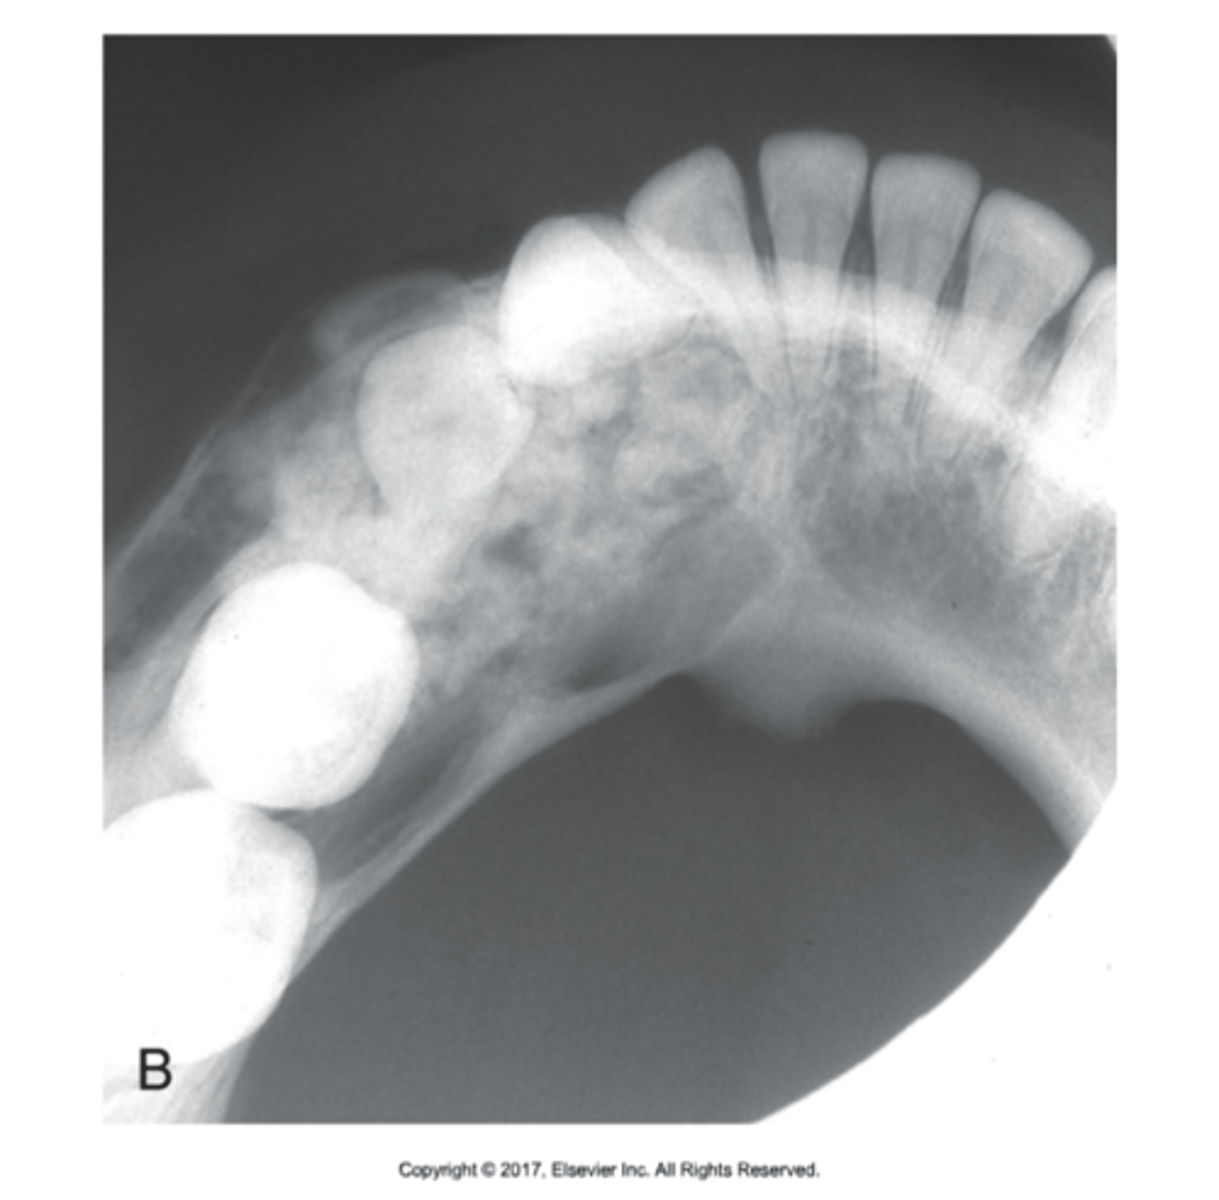

what is this?

what is this radiolucent area in the image?